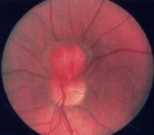

Refer to the pictures above for question 1 & 2

1. Other ocular manifestations of the above condition

include:

2. Other manifestations of this condition include: